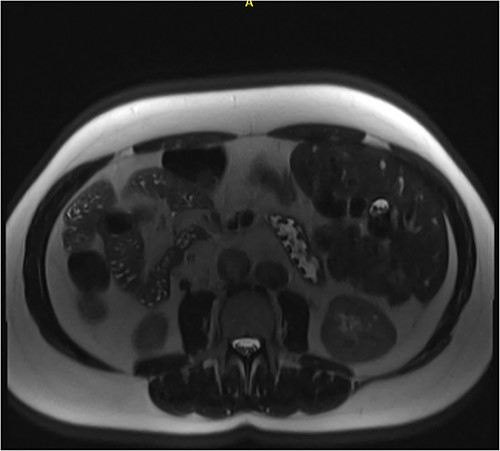

Following examination, a magnetic resonance cholangiopancreatography (MRCP) test was requested to exclude choledocholithiasis. 24 hours later, this confirmed gallstones, with 10 mm saccular dilatations near the hilar confluence (Figs 1 and 2). This dilatation was non-progressive according to previous scans, with unaffected pancreatic and intrahepatic ducts. Dilated portal vessels and varices were discovered to be directly communicating with the gallbladder fossa, suggestive of portal venous communication.

Axial MRCP scan demonstrating small stones in a contracted gallbladder.